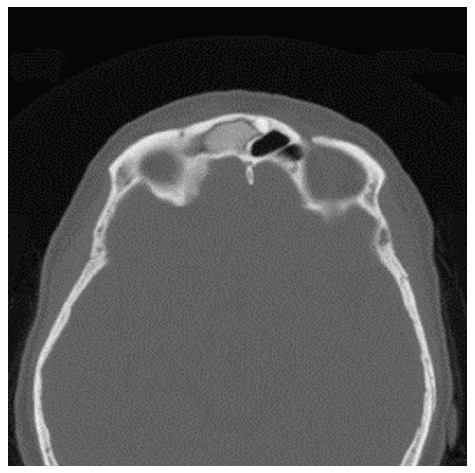

Хондрома на КТ представляется как объемное образование гетерогенной плотности с четко очерченными границами и очагами минерализации (рисунок 9).

Рис. 9. КТ носа и околоносовых пазух, коронарная (А) и аксиальная (Б) плоскости. Хондрома полости носа. Опухоль исходит из носовой перегородки, обтурирует правую половину носа, имеет четкие границы. Определяется смещение медиальной стенки правой верхнечелюстной пазухи, вторичные воспалительные изменения в верхнечелюстной и лобной пазухах справа